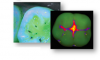

As another safe diagnostic tool, fluorescence technology can be used as an imager or scanner, each with its own capabilities. The imager bathes teeth and tissue in a blue light that highlights abnormalities (Figure 2), while the scanner aims a yellow-red light directly onto areas of interest. These devices can be used to detect bacteria, plaque, enamel, and dentin through fluorescence stimulation. Imagers utilize a range of colors or numbers to indicate the range of conditions (Figure 3), whereas scanners display a number correlated to the degree of demineralization. Fluorescence devices are indicated for occlusal caries; however, they are not indicated for interproximal caries or for use around restorations, nor do they detect fractures.3,4

Fig 2.  Example of image taken with fluorescence imager technology.

Figure 2

Fig 3. Oral conditions appear as a range of colors with fluorescence imager technology.

Figure 3